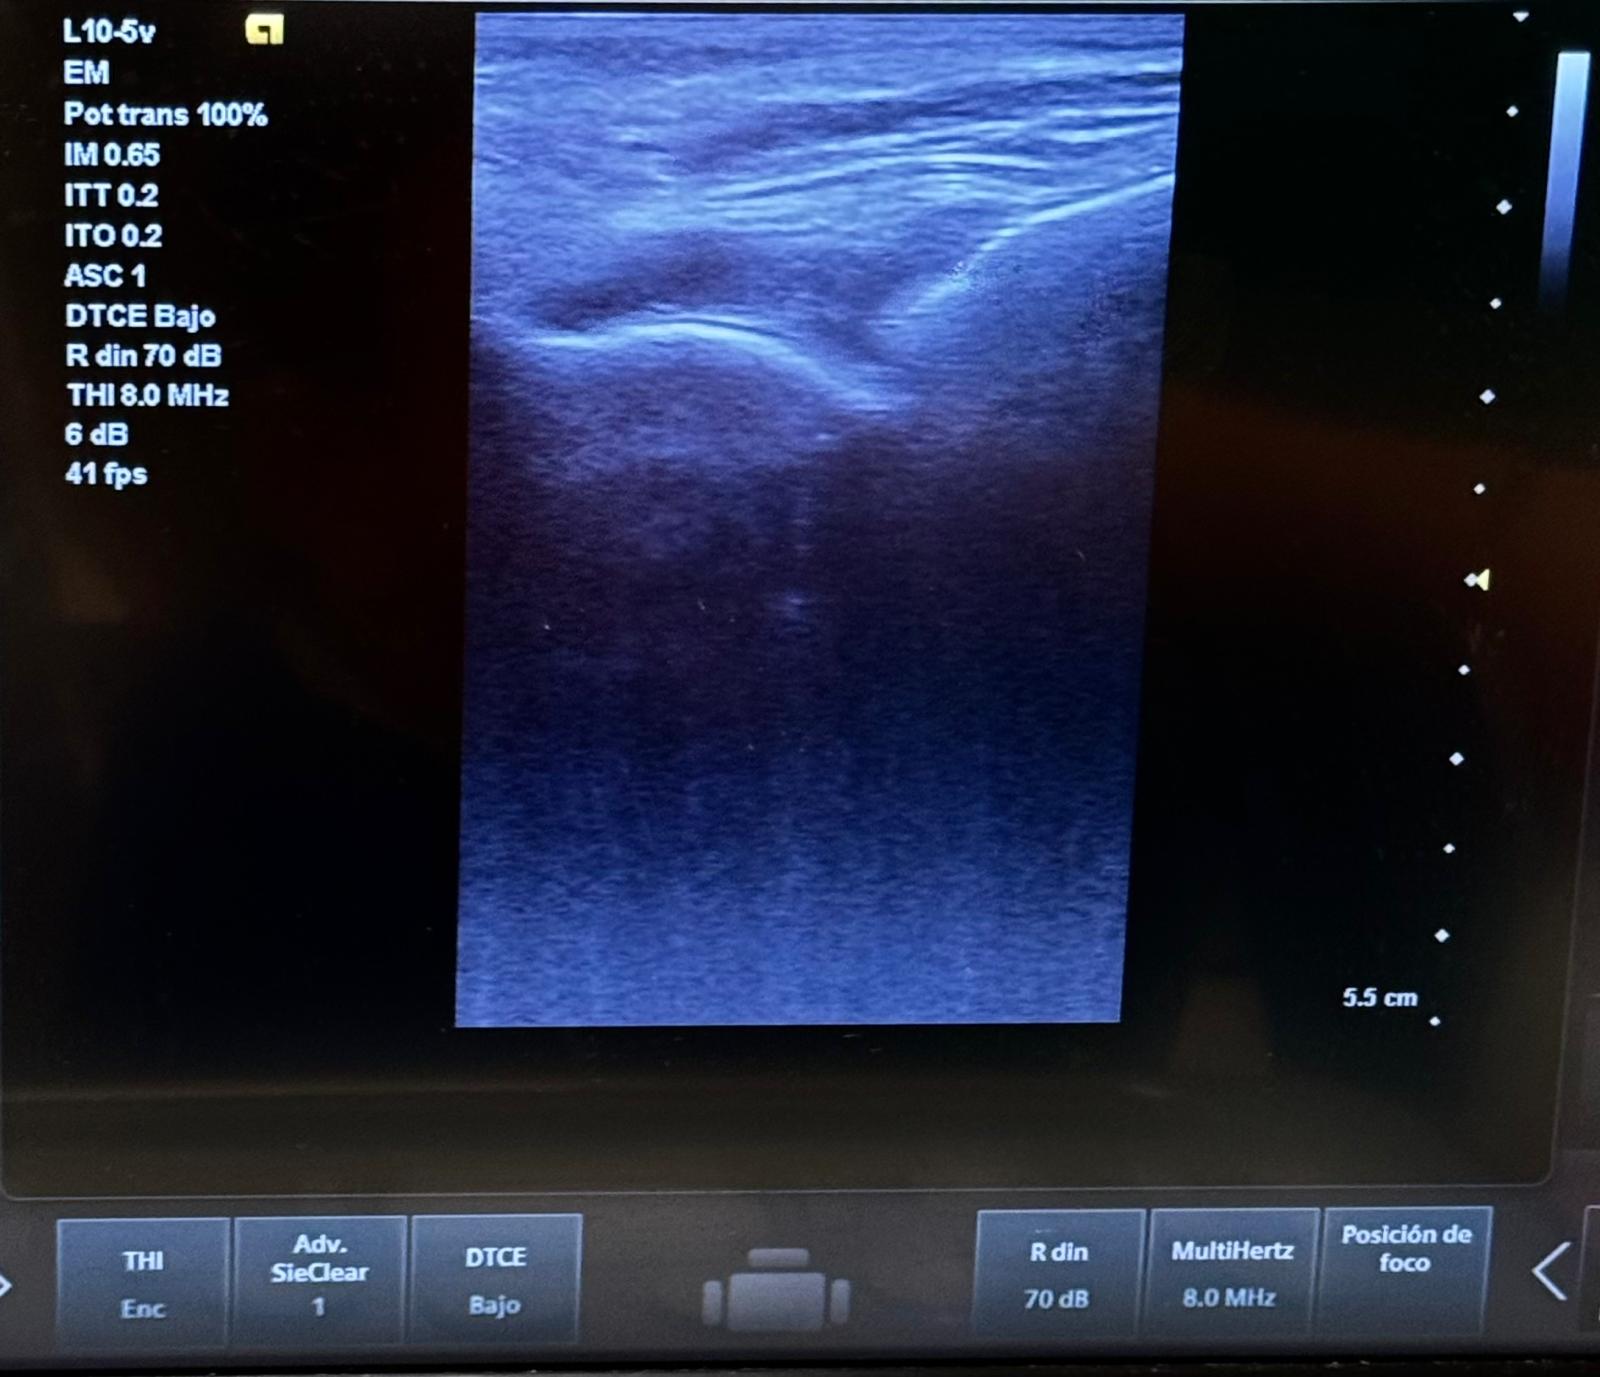

Pruebas complementarias:

La artritis séptica requiere diagnóstico rápido para prevenir daños articulares permanentes. En medicina de familia, la identificación precoz de signos como dolor, tumefacción y calor local es clave para derivar adecuadamente. La analítica, la ecografía y la artrocentesis son esenciales para confirmar el diagnóstico y guiar el manejo inicial en urgencias.